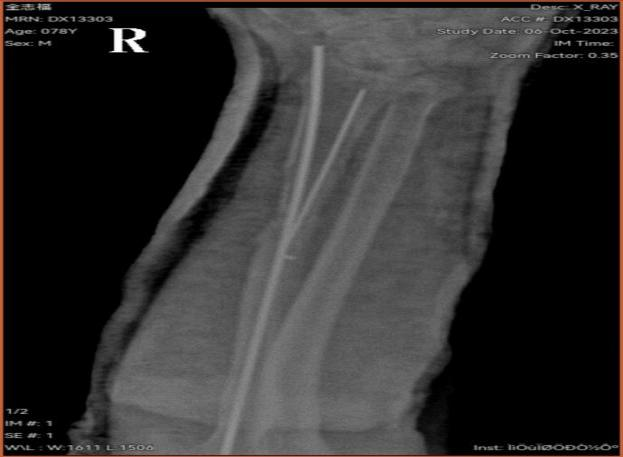

在张平院长的带领下,天柱县中医院骨伤科及手术室麻醉科团队建立绿色急诊快速通道经过三个多小时的手术,患者手术满意顺利安返病房。术后患者及家属非常感激,直言天柱县中医院医师敢于担当、技术过硬、为民解忧,在家门口就能解决高难度手术。术后骨伤科医护团队继续为该患者进行专业的专科治疗护理。目前患者已经顺利康复出院了。